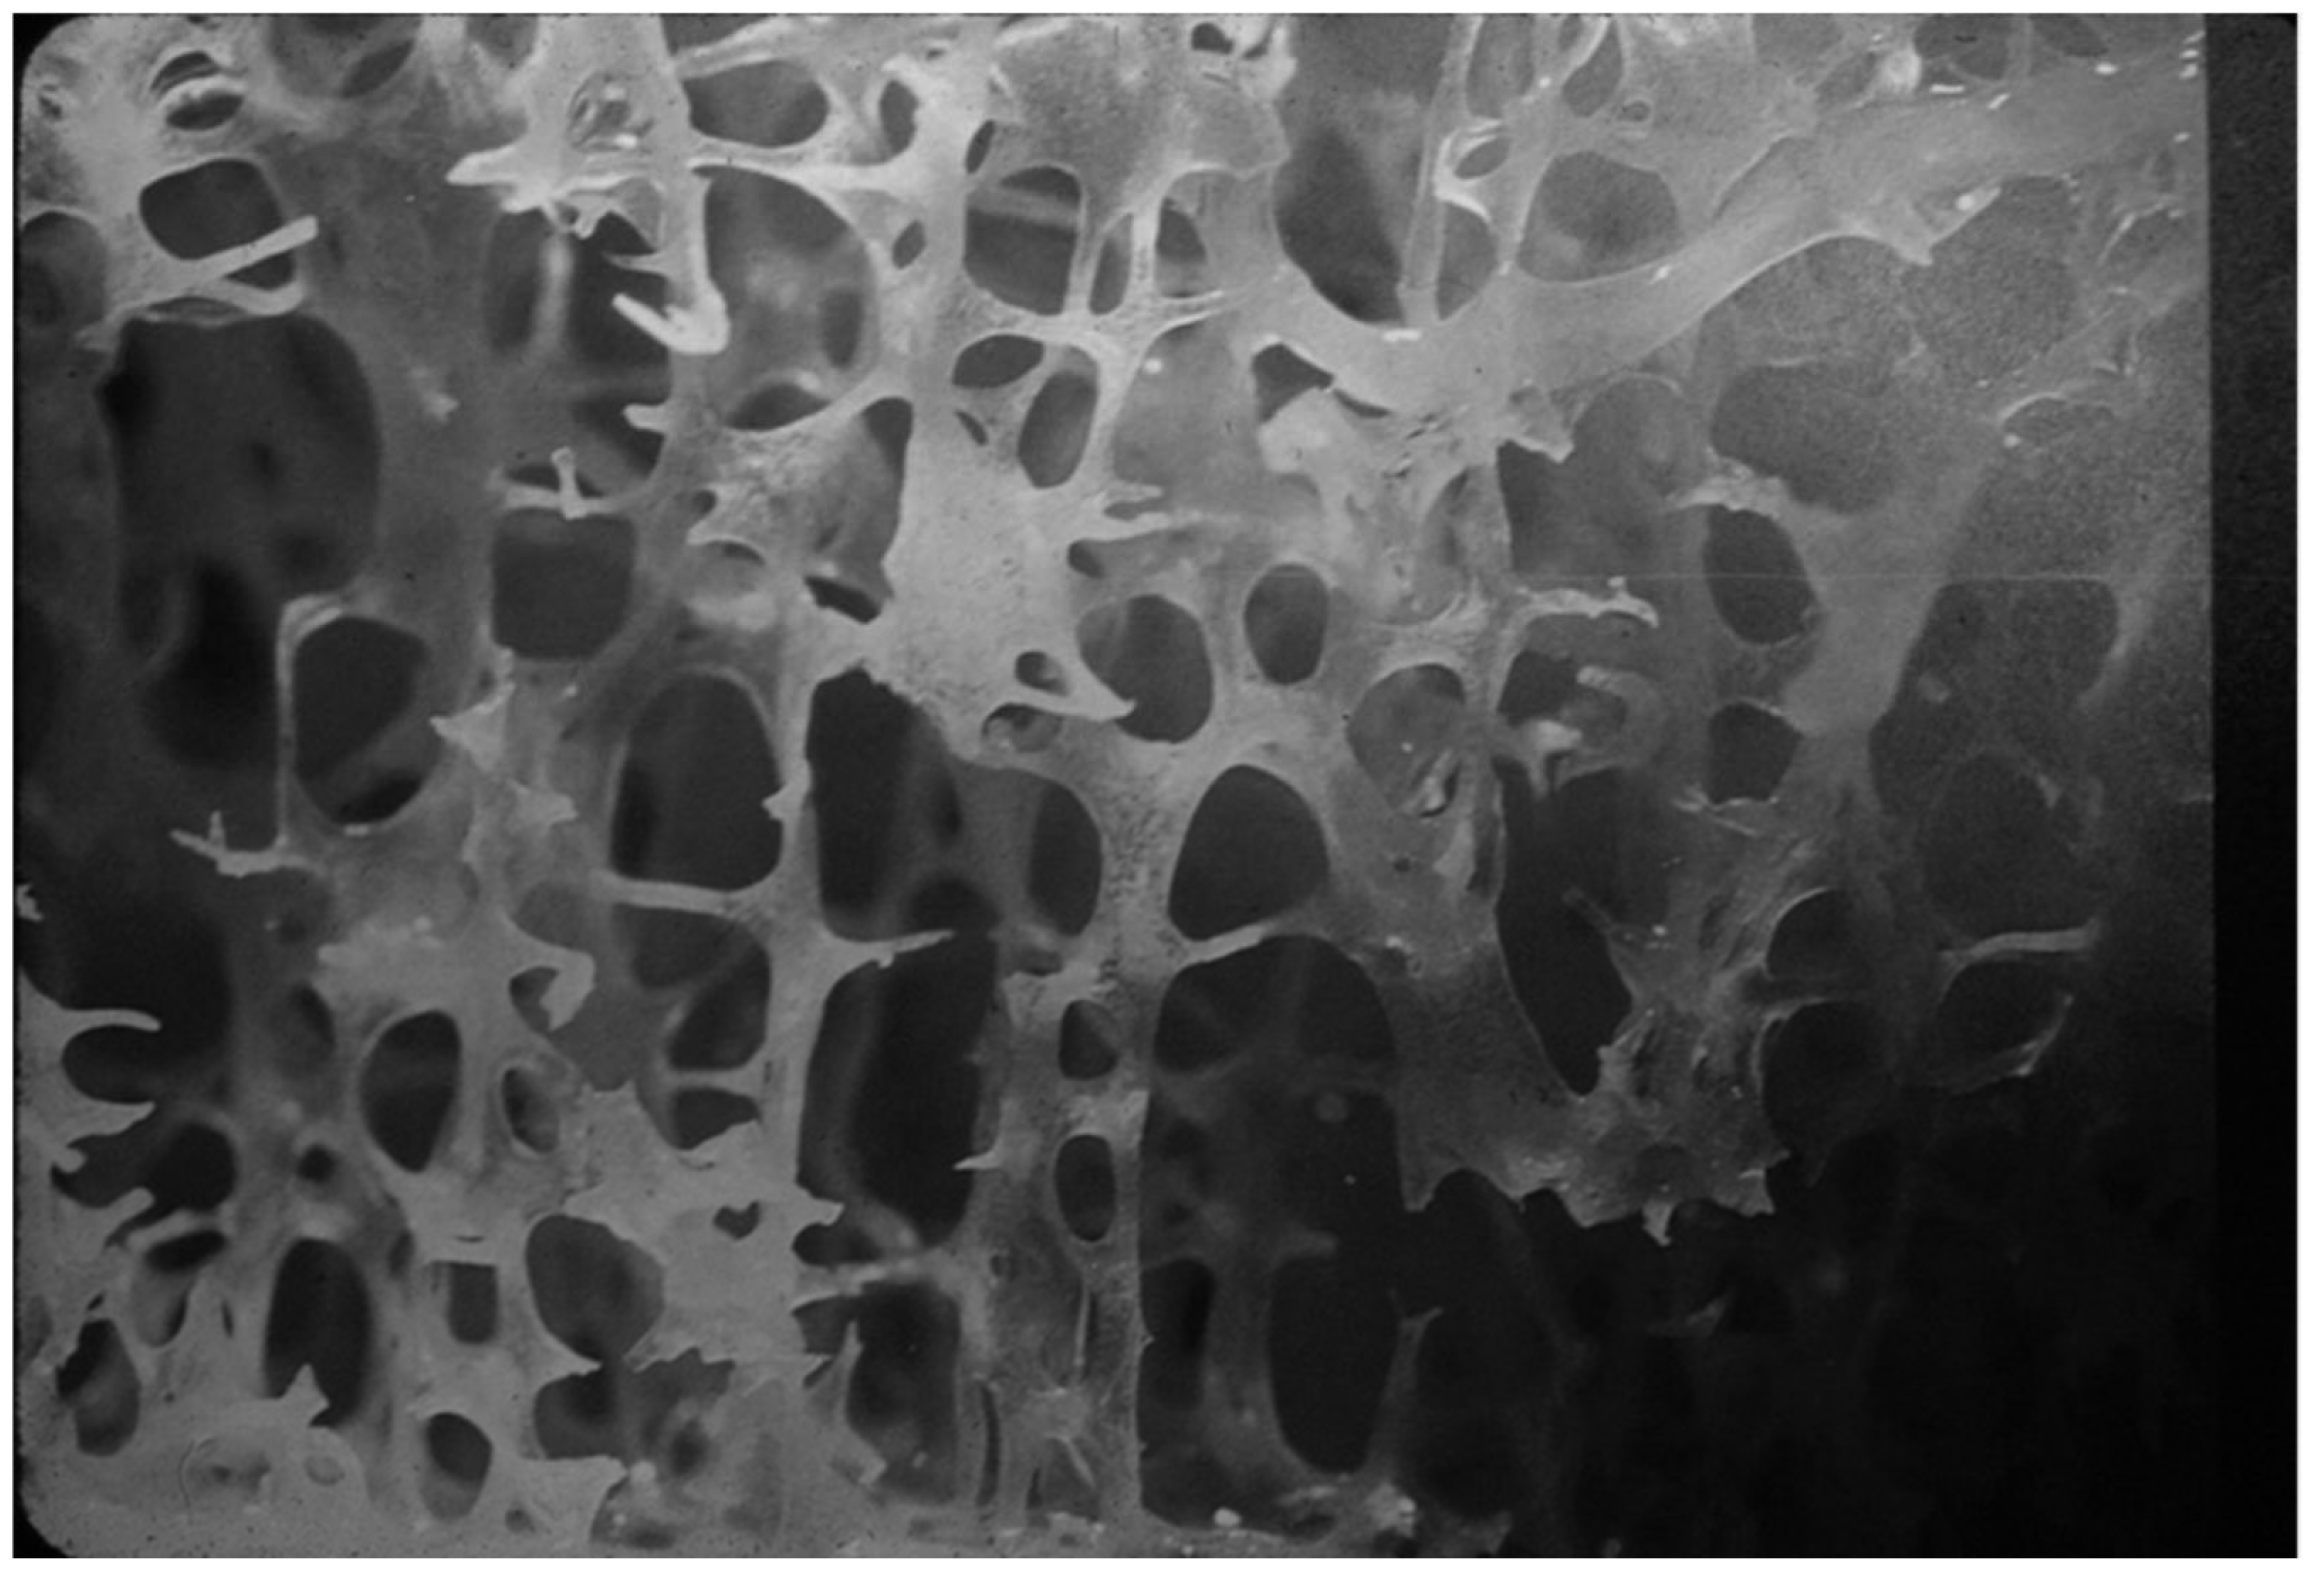

4.1.2. Levels of Bone Organization—Microarchitecture

- Goldstein, S.A.; Goulet, R.; McCubbrey, D. Measurement and significance of three-dimensional architecture to the mechanical integrity of trabecular bone. Calcif. Tissue Int. 1993, 53 (Suppl. 1), S127–S132; discussion S132–S133. [Google Scholar] [CrossRef]

- Ammann, P.; Laib, A.; Bonjour, J.P.; Meyer, J.M.; Rüegsegger, P.; Rizzoli, R. Dietary essential amino acid supplements increase bone strength by influencing bone mass and bone microarchitecture in ovariectomized adult rats fed an isocaloric low-protein diet. J. Bone Miner. Res. 2002, 17, 1264–1272. [Google Scholar] [CrossRef] [PubMed]

- Ammann, P.; Bourrin, S.; Bonjour, J.P.; Meyer, J.M.; Rizzoli, R. Protein undernutrition-induced bone loss is associated with decreased IGF-I levels and estrogen deficiency. J. Bone Miner. Res. 2000, 15, 683–690. [Google Scholar] [CrossRef] [PubMed]

- Dalle Carbonare, L.; Giannini, S. Bone microarchitecture as an important determinant of bone strength. J. Endocrinol. Investig. 2004, 27, 99–105. [Google Scholar] [CrossRef]